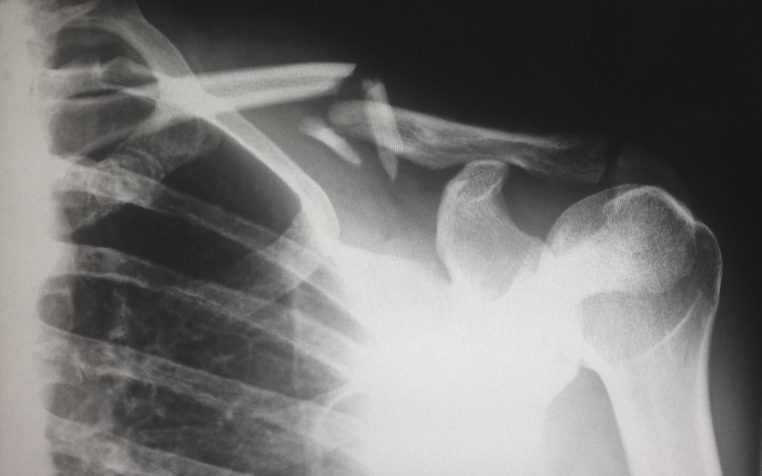

Des scientifiques chinois créent « Bone 02 », un gel qui répare les fractures en 3 minutes

L’adhésif en gel promet de souder les os fracturés sans chirurgie ni plaques métalliques, en seulement trois minutes. Il a déjà donné des résultats concluants sur plus de 150 patients.

Dans un laboratoire de l’Université de Zhejiang, à l’est de la Chine, une équipe de chercheurs vient de franchir une étape qui pourrait révolutionner le traitement des fractures osseuses. Ils ont mis au point Bone 02, un gel adhésif capable de réparer un os en seulement trois minutes, sans intervention invasive ni matériel métallique.

Testé sur plus de 150 patients, Bone 02 a démontré une efficacité remarquable. Le gel maintient les os solidement et pourrait remplacer certains implants métalliques. Par ailleurs, il réduit les risques d’infections ou de réactions indésirables.

Des fractures réparées en seulement trois minutes

Le protocole est d’une rapidité inédite : lors des essais, les fractures ont été stabilisées en à peine trois minutes. Autre atout, le produit se résorbe naturellement à mesure que l’os guérit, évitant ainsi une seconde opération.

Jusqu’ici, les traitements traditionnels se limitaient à stabiliser les fractures sans véritablement recoller les os. Avec Bone 02, biologie et ingénierie s’allient pour offrir une solution rapide et efficace, qui suscite déjà un vif enthousiasme chez les médecins et chercheurs.